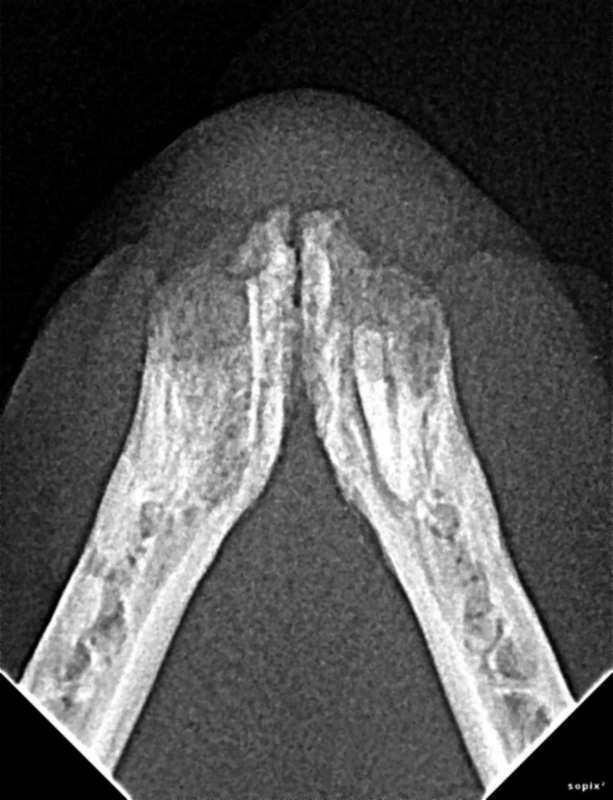

Repair of Maxillofacial Fracture

Pets can be involved in trauma that can cause fractures to their head, teeth, and jaw bones. Correctly repairing these fractures is extremely important for your pet to have normal function of their mouth. If a jaw fracture is allowed to heal in an abnormal position, your pet may have great difficulty chewing and can be in significant pain. Many fractures can be successfully treated with minimally invasive oral procedures, but more complicated cases may require bone plating techniques. The Center offers cone beam CT imaging which provides extremely detailed images of the bones of the head and skull. Advanced imaging with CBCT facilitates selection of the best surgical technique to get your pet back to eating and comfort as soon as possible.